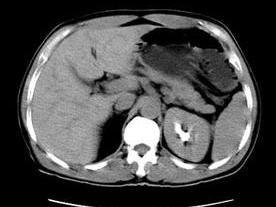

超音波、CT、MRI檢查可明確區分增大的腎是積水還是實性腫塊亦可發現壓迫泌尿系統的病變,由於超聲檢查已經普及且為無創傷性,可以在尿路造影以前進行。放射性核素掃描和腎圖亦可用於腎積水的診斷。對動力性梗阻病例,可在尿路造影是觀察腎盂、輸尿管蠕動及排空情況。神經原性膀胱可見膀胱造影形似"寶塔",有成小梁和假性憩室。